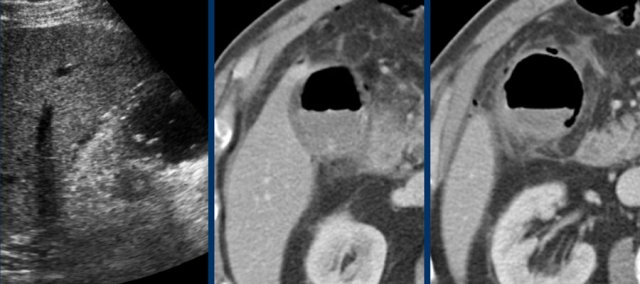

Images of a young woman with a biliary colic for 8 hours.

US shows an impacted stone and hydrops.

The patient went walking for an hour and US was repeated.

The stone was loose, and reperfusion edema was visible as silent witnesses of the colic.

CRP remained normal.